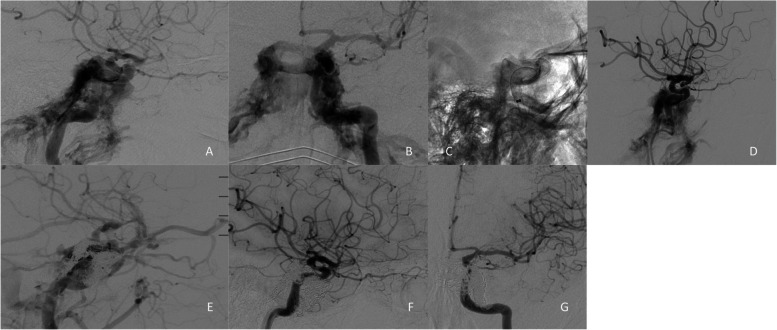

Abstract Image